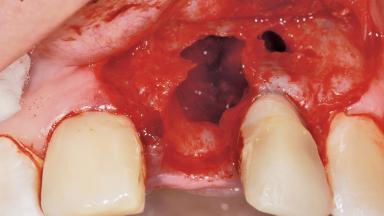

Late Flapless Placement of an Implant in a Maxillary Left Central Incisor Site

A 39-year-old male patient presented with a chief complaint of discomfort and gingival discoloration around his maxillary left central incisor. He was in good general health and was a non-smoker. His past dental history was significant because of the traumatic fracture of tooth 21 in a sporting accident at age 13. Initial dental treatment included endodontic therapy and a full-coverage restoration. The patient became symptomatic 5 years later, when structural failure of the tooth resulted in the dislodgment of the crown. Endodontic retreatment, apical surgery, and post-and-core restoration were performed.

Bone Volume Deficient horizontally, requiring prior grafting